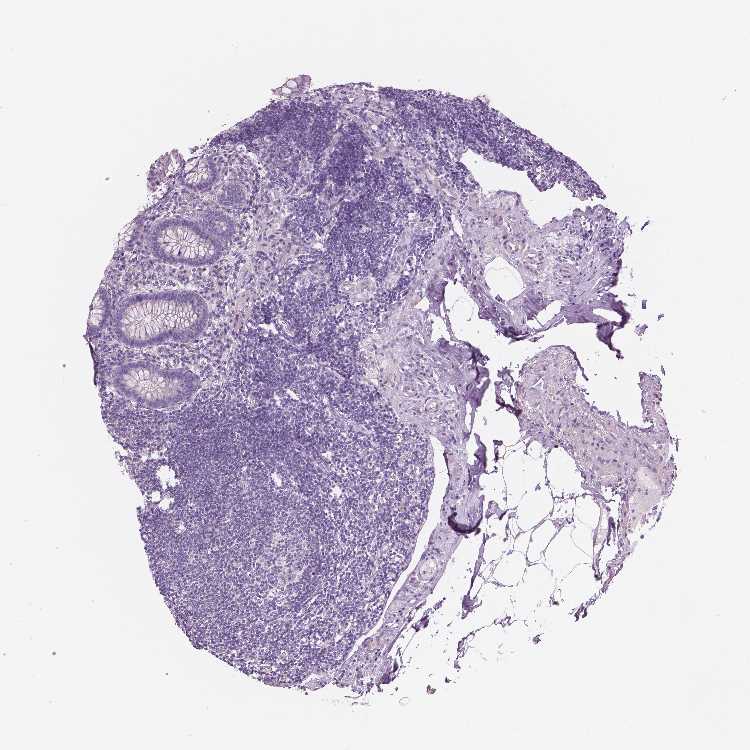

APPENDIX - Expression summary

Appendixi

On the top, protein expression in current human tissue, based on all annotated cell types, is reported with the units not detected (n), low (l), medium (m) and high (h). Underneath, protein expression in each annotated cell type are reported using the same units.

Protein expression data is based on knowledge-based annotation. For genes where more than one antibody has been used, a collective score is set.

APPENDIX - Antibody stainingi

Antibody staining in the annotated cell types in the current human tissue is reported as not detected, low, medium, or high, based on conventional immunohistochemistry profiling in selected tissues. This score is based on the combination of the staining intensity and fraction of stained cells.

Each image is clickable and will lead to virtual microscopy that enables deeper exploration of all samples and also displays staining intensity scores, fraction scores and subcellular localization as well as patient and tissue information for each sample.

Glandular cells Not detectedNot detected

Lymphoid tissue Not detectedNot detected